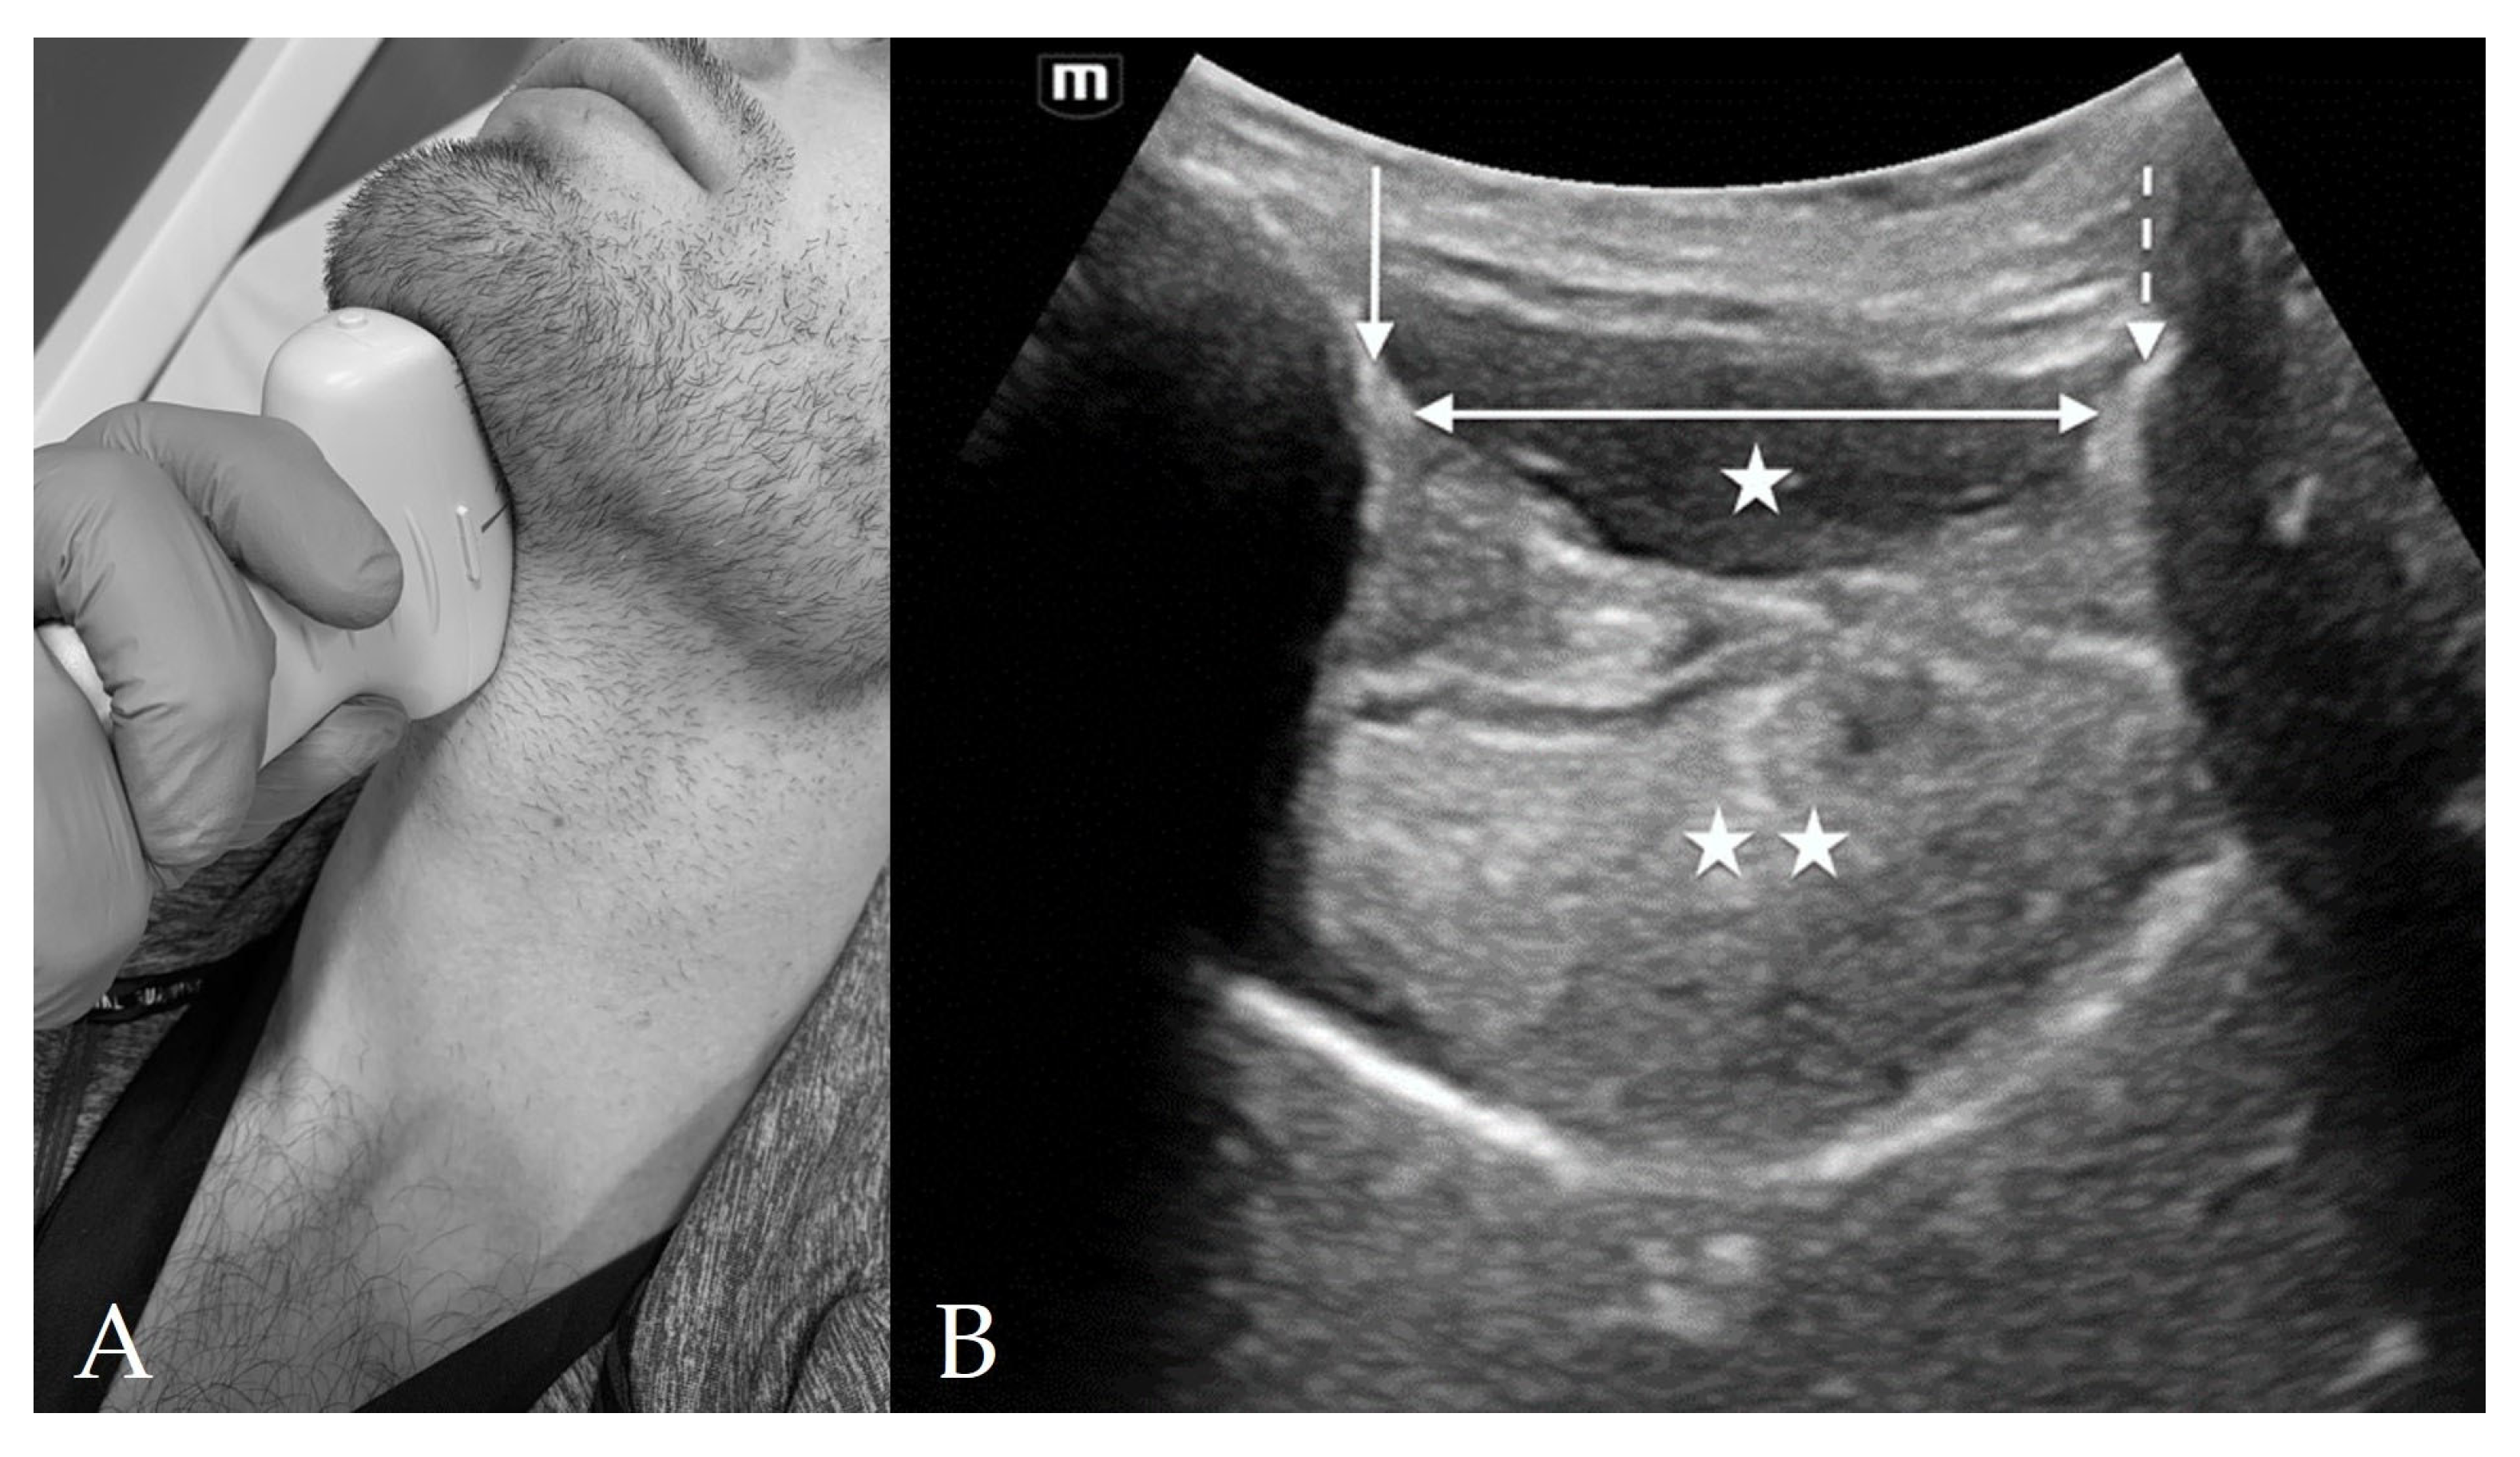

4.1. Suprahyoid View

4.2. Thyrohyoid View

4.3. Thyroid View

4.4. Cricothyroid View

4.5. Suprasternal View